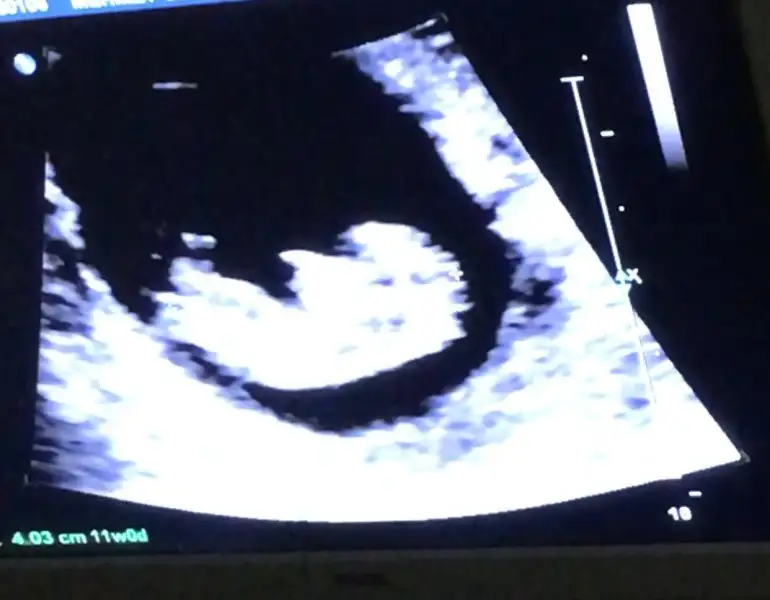

Gözün aydın cnm maşallahKızlar muayene oldum bebeğim hep geriden gelirken bu hafta ileri girmiş 10+3 üz normalde ama ultrasonda 11+0 çıktı 4.03 cm olmuşuz. Hareket ediyordu nubuna baktım bana kız gibi geldi bide siz bakın bakalım

Nubuna nasıl bakılıyor ki nub ne?Kızlar muayene oldum bebeğim hep geriden gelirken bu hafta ileri girmiş 10+3 üz normalde ama ultrasonda 11+0 çıktı 4.03 cm olmuşuz. Hareket ediyordu nubuna baktım bana kız gibi geldi bide siz bakın bakalım